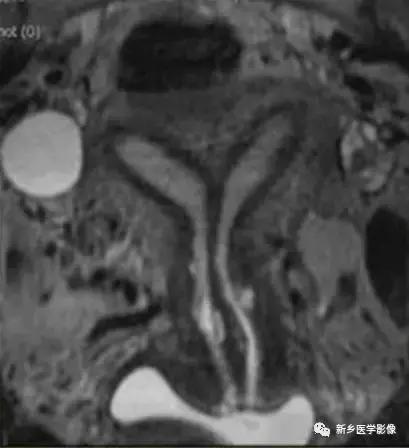

双角子宫:不完全型,宫底凹陷,上部子宫不融合,子宫纵隔未达宫颈内口水平。

双角子宫:完全型